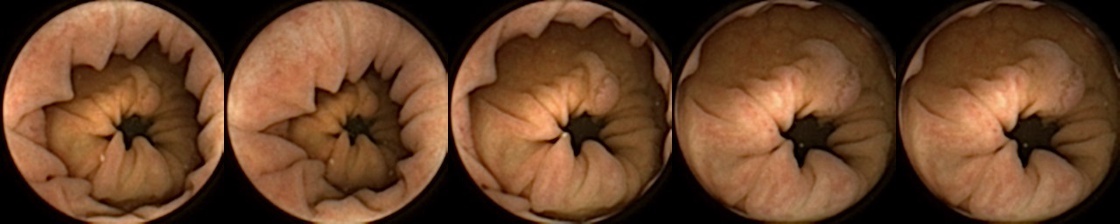

Similarly, we consider examples for the MIV model based on SimCLR pretraining using the pretrained ConvNext backbone in Figure 4. The model has a test accuracy of 86.26% for DBA L1 with 2 heads. Here we note again a similar trend by looking at the True Positive and False Negative examples as observed before, where a significant difference in the query image when compared with the target images can lead to a failure to identify the same polyp images in the five examples. A look at the False Positive examples affirms that the task remains challenging, as evidenced by the model’s occasional misclassifications in ambiguous cases.

True Positive False Negative

False Positive True Negative

Figure 4: True Positives (Pred = true, Label = true), False Negatives (Pred = false, Label = true), False Positives (Pred = true, Label = false),True Negatives (Pred = false, Label = false) for the DBA L1(h=2) model applying SimCLR using the ConvNeXt backbone. In each row, the leftmost image is the query and the 4 images to the right of each query are the target images.